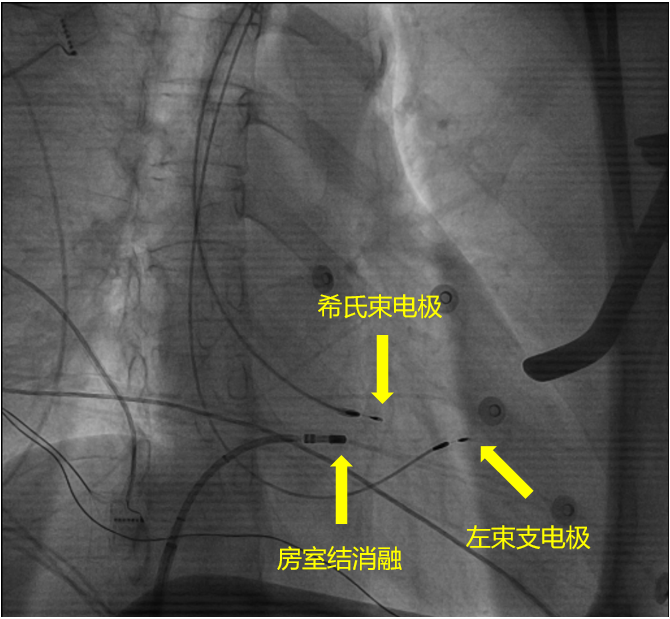

手術影像:國際先進的房室結消融+希浦系統起搏

消毒、鋪單、麻醉,在李海鷹主任的指揮下,所有工作都有條不紊地進行着。一般來說,常規起搏器電極植入大多以右心室心尖部為起搏點,但部分患者在植入起搏器後,會出現左右心室不同步、起搏依賴等情況。而心臟傳導系統中的希氏束,相當於左右心室間的「高速通道」,把心肌細胞連接成一個整體,讓心肌細胞同步「跳動」,從而實現心臟的正常跳動。如果能將起搏器放在希氏束上,那就完美了。

但它最大的難點也在於此,如何精準定位希氏束和左束支,找到心臟當中這條極窄的「信息高速公路」,並把電極精準牢靠地固定在上面,對心臟電生理醫師來說是一項極大的挑戰。

作為國內頂尖的起搏電生理專家,李海鷹主任對希浦系統起搏可謂是庖丁解牛、輕車熟路,不到一個小時就找到了希氏束和左束支並成功植入了電極,速度之快令人驚嘆。在房室結被成功阻斷後,心電監護立即響起了「嘀……嘀……嘀」的心跳聲,每一聲都那麼精準而穩定,彷彿時鐘一樣。